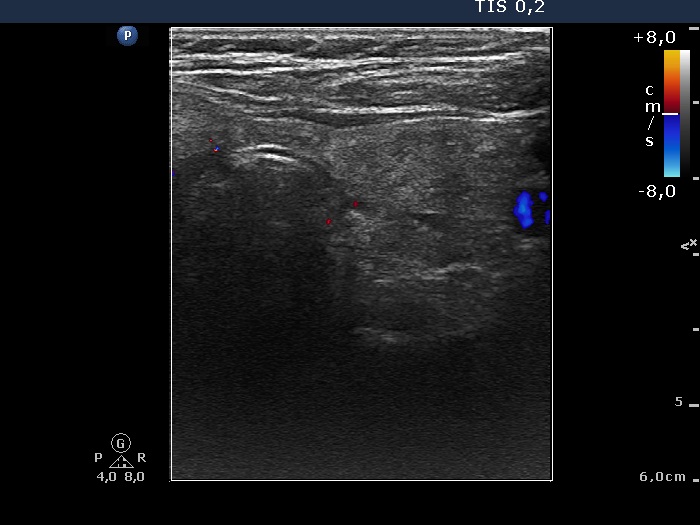

100 consecutive patients with thyroid nodule - Case 26. (ultrasonographic picture 6)

Left horizontal scan, color Doppler mode. The lobe is avascular.